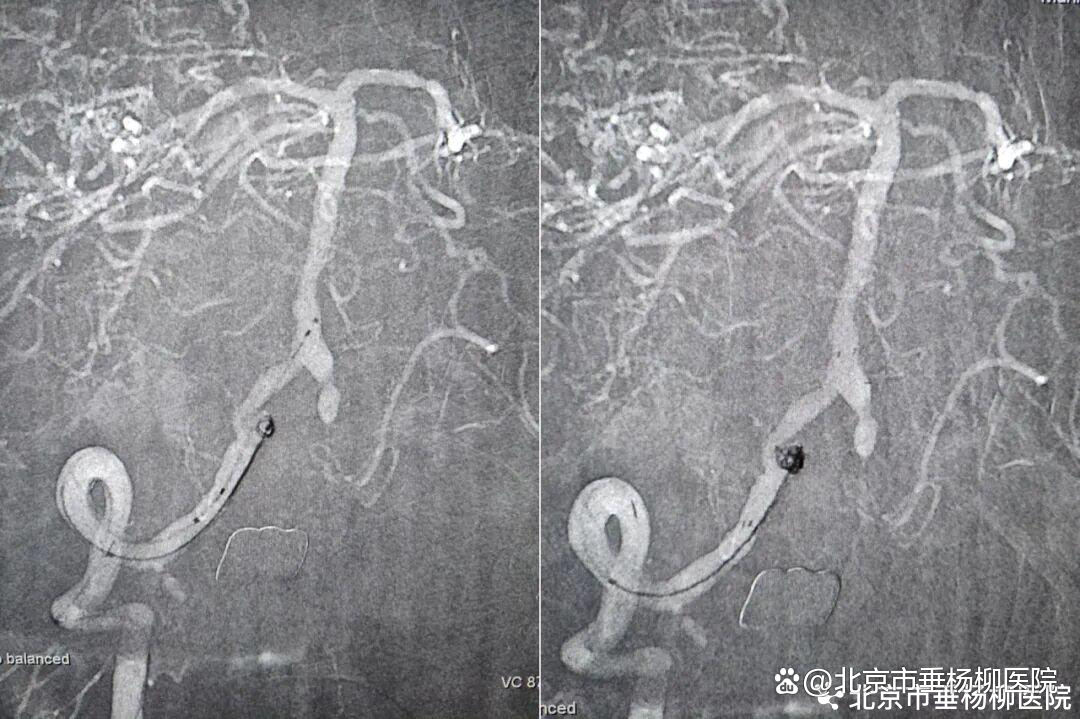

第二步,处理动脉瘤,拆除不定时炸弹。医生将微导管超选择进入动脉瘤腔内,依次填入数枚弹簧圈,直至动脉瘤完全栓塞,不再显影。因为动脉瘤瘤颈宽,故于载瘤动脉内植入了支架以达到致密栓塞,降低复发率。

第三步,解除狭窄,恢复血流。选择合适尺寸的球囊扩张式支架,精准释放于右侧椎动脉起始部狭窄段。

第四步,最终验证。再次造影显示:狭窄消失,支架位置良好。动脉瘤不显影,弹簧圈致密填塞。